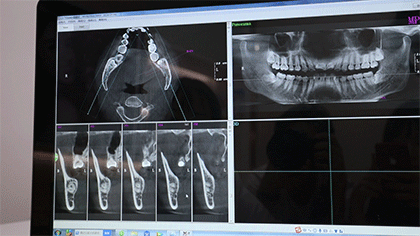

采用先进的3D口腔CT检查设备

只要短短1分钟

牙齿的高清照就出炉了

并同步传输到医生电脑

牙齿存在的问题一目了然